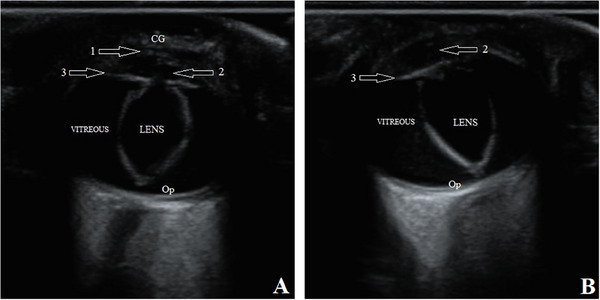

先天性眼睛畸形是不常见的,在一些犬种,没有证据表明他们的发生。本报告旨在描述中亚牧羊犬复杂小眼症的临床和超声表现。本文介绍了两窝3只2个月大的雌性中亚牧羊犬幼犬,因其主人自诉出生后眼睛异常而被转介至我院教学医院。临床检查幼犬反应灵敏,生命体征正常,未见其他结构异常。在所有三只狗的眼科评估中,球体出现双侧小且凹陷在眼眶中。在幼犬眼睛的超声波中,晶状体厚度和眼球轴向长度分别大于和小于同一年龄和品种的健康幼犬的眼睛测量值。此外,在所有三只小狗中,晶状体位于玻璃体腔内,并垂直于其自然轴移位。在此基础上,诊断为双侧复杂性小眼和先天性晶状体异位两种病因不明的眼部畸形。由于这种畸形可能与犬舍内的高度近亲繁殖以及环境和遗传因素有关,这些情况可以通过育种努力和育种前筛选计划加以限制。

Congenital eye malformations are uncommon and in some dog breeds, there is no evidence of their occurrence. This report aimed to describe the clinical and ultrasonographic findings of complex microphthalmia in Central Asian Shepherd dogs. Three 2-month-old female Central Asian Shepherd puppies from two litters were referred to our teaching hospital with the owner's complaint of eye abnormalities since birth. The puppies were alert on clinical examination, the vital signs were normal, and no other structural abnormalities were observed. In the ophthalmological assessments of all three dogs, the globe appeared bilaterally small and sunken in the orbit. In the ultrasound of the puppies' eyes, the lens thickness and axial length of the globe were greater and less than the values measured in the eyes of a healthy puppy of the same age and breed, respectively. Moreover, in all three puppies, the lenses were located in the vitreous chamber and displaced perpendicular to their natural axis. On the basis of this, bilateral complex microphthalmia and congenital ectopia lentis, two ocular malformations of unclear etiology, were diagnosed. Due to the possibility of an association between such malformations and a high grade of inbreeding in kennels, as well as environmental and genetic factors, these conditions can be limited by breeding efforts and pre-breeding screening plans.